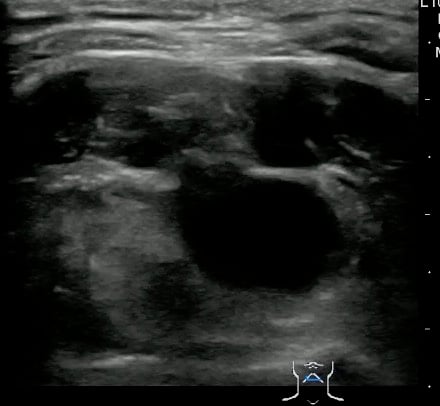

Thyroglossal duct cyst26

- Thyroglossal duct cysts typically related to hyoid bone:

- Often midline

- 25%-suprahyoid-submental region

- 75%-Infrahyoid or at the level of hyoid

- Variable sonographic appearance:

- Well-circumscribed anechoic cyst

- Increased through transmission

- Hypoechoic with internal debris

- No internal vascularity

- Heterogeneous pattern seen in repeated infections and hemorrhage due to prior aspirations

- Pseudo-solid echogenic appearance from proteinaceous contents secreted by epithelial lining

- Figure 34 and 35. Thyroglossal Duct Cyst

Video 22. Thyroglossal Duct Cyst